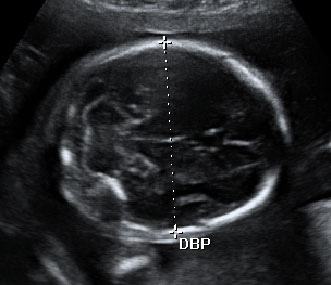

Ecografía Embarazo 4D - SEMANA 20